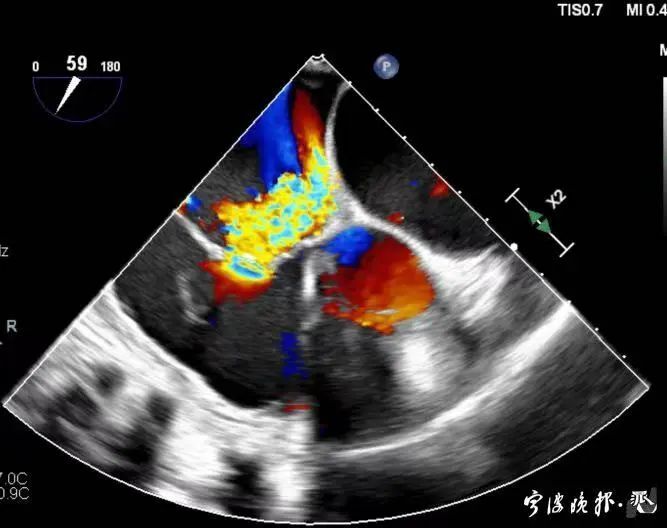

術(shù)前食道心超示三尖瓣重度反流